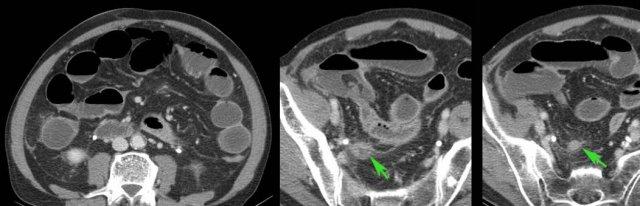

Người đàn ông 66 tuổi này nhập viện với đau bụng dữ dội kèm viêm phúc mạc toàn thể và CRP 550.

Siêu âm chỉ phát hiện quai ruột non giãn, CT được thực hiện với nghi ngờ thiếu máu mạc treo.

CT cho thấy viêm ruột thừa (mũi tên) với đầu ruột thừa thủng và nhiễm bẩn bốn góc phần tư của khoang phúc mạc.

Ở bệnh nhân 16 tuổi này với đau hố chậu phải, các hạch bạch huyết mạc treo to được bao quanh bởi một ít mỡ đang viêm (*) là dấu hiệu siêu âm duy nhất và không xác định được ruột thừa.

CT xác nhận các hạch to (đầu mũi tên), nhưng phát hiện thêm ruột thừa đang viêm (mũi tên), xuất phát từ manh tràng ở vị trí sâu trong tiểu khung.

Bệnh nhân trẻ bị viêm ruột thừa cấp thường có hạch bạch huyết mạc treo to thứ phát.